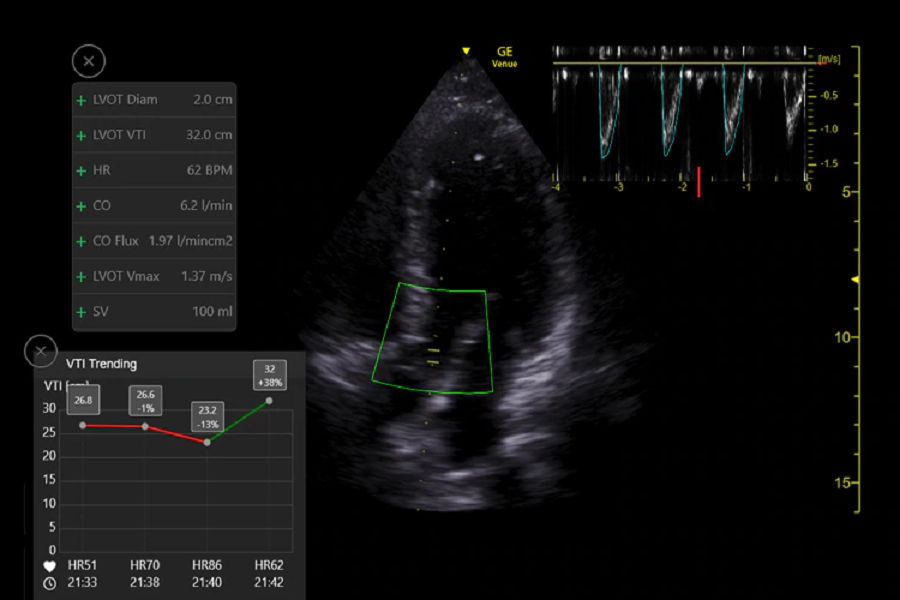

Bis zu 82 % Zeitersparnis mit dem Venue Auto VTI-Tool im Vergleich zu manuellen Methoden8

Im hämorrhagischen Schockmodell zeigte das Venue Auto VTI-Tool eine bessere Korrelation mit dem mittels Thermodilution gemessenen CO als mit manuellen echokardiographischen Messungen.8